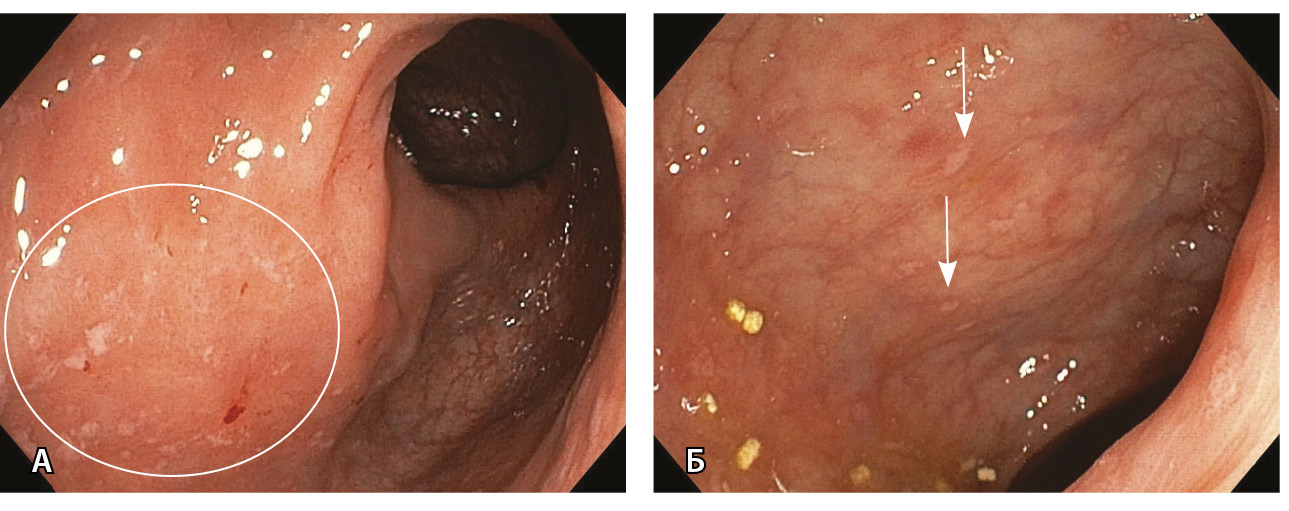

Рис. 2. Очаговый геморрагический колит после перенесенной инфекции SARS-CoV-2. У больной 74 лет эндоскопически визуализируются очаговые геморрагии (отмечены стрелками) на фоне гиперемированной слизистой, сохраненный сосудистый рисунок

Рис. 3. Эндоскопическая картина язвенного колита умеренной активности (А; больной 38 лет) и высокой активности (Б; больной 47 лет), впервые возникшего после перенесенной инфекции SARS-CoV-2

3. Fig. 2. Focal hemorrhagic colitis after SARS-CoV-2 infection in a 74-year old patient. At endoscopy: focal hemorrhages (arrows) within hyperemic mucosa; no abnormalities in vascular structures

4. Fig. 3. Endoscopic manifestations of moderately active ulcerative colitis (А; a 38-year old patient) and highly active ulcerative colitis (B; a 47-year old patient), newly diagnosed after the SARS-CoV-2 infection